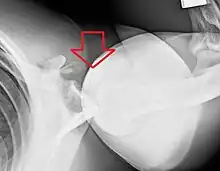

Anterior (forward)

In over 95% of shoulder dislocations, the humerus is displaced anteriorly.[6] In most of those, the head of the humerus comes to rest under the coracoid process, referred to as sub-coracoid dislocation. Sub-glenoid, subclavicular, and, very rarely, intrathoracic or retroperitoneal dislocations may also occur.[7]

Anterior dislocations are usually caused by a direct blow to, or fall on, an outstretched arm. The person typically holds his/her arm externally rotated and slightly abducted.

A Hill–Sachs lesion is an impaction of the head of the humerus left by the glenoid rim during dislocation.[5] Hill-Sachs deformities occur in 35–40% of anterior dislocations. They can be seen on a front-facing X-ray when the arm is in internal rotation.[8] Bankart lesions are disruptions of the glenoid labrum with or without an avulsion of bone fragment.

An anterior dislocation of the shoulder